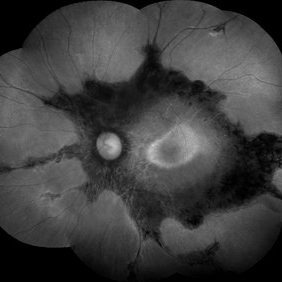

Female patient, 21-years-old, with complaint of low vision in the right eye for 3 years. According to information from the patient's history, at the time she noticed the low vision, it also coincided with a picture of a strong urinary infection as well as episodes of constant tonsillitis. Yes, the patient did not seek medical attention and self-medicated with antibiotics. In ophthalmologic evaluation, as well as examinations of color retinography and ocular fundus autofluorescence, important pigmentary alterations were observed following vascular arches with pigment mobilization in osteoclasts (aspect of a unilateral pigmentary retinitis secondary to the inflammatory process). Which suggested inflammatory process sequelae. Through the laboratory tests, he had positive (+) confirmation for SYPHILIS NEURORETINOPATHY .

Photographer: JEFFERSON R SOUSA - Study Center and Ophthalmological Research Dr. Andre M V Gomes, Institute Dr. Suel Abujamra São Paulo-Brazil

Imaging device: Fundus camera Topcon TRC-50 DX, Imaginet 5.0, angle de 50 graus. Flash 100 / Mosaic with 10 images.

Condition/keywords: autofluorescence imaging, neurosyphilitic optic atrophy, retinitis pigmentosa, syphilis, syphilis neuroretinopathy